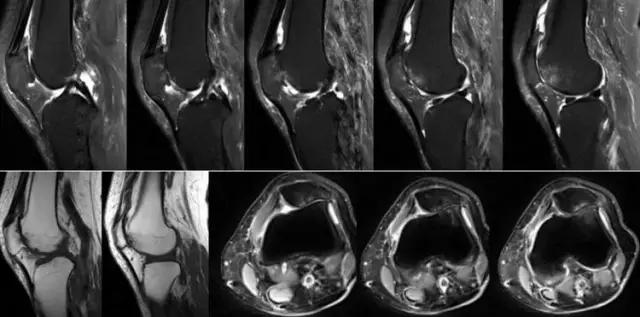

地中海贫血与白血病均为血液系统的问题,主要表现在骨髓,疾病的发病机理有别,MRI表现也不相同;我们可能不是很熟悉这些疾病,也能够从MRI发现区别。图1:正常膝关节 图2:地中海贫血 图3:白血病

利用自身对比——

我们可能都不熟悉T1、T2,怎么办?当我们发现有问题后,利用照片上图像的对比,推测病变的可能也是一种诊断方法。病例:黄XX,女,39岁,左膝关节反复交锁1年。图1:肿物信号与骨信号一样图2:肿物信号与骨信号一样图3:肿物信号与骨信号不一样 肿物应该与骨相关,但不是骨性,推断:膝关节滑膜软骨瘤。手术后得到证实。